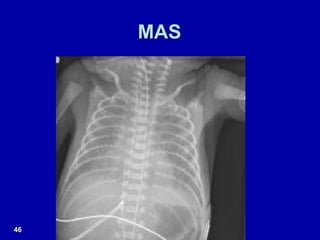

X-ray - MAS

MAS

46